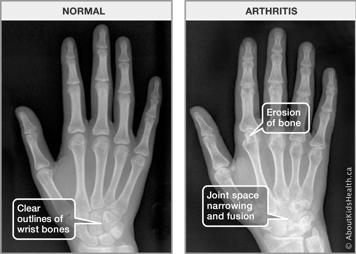

If the inflammation of JIA is not treated, it can lead to permanent damage of your joint. Damage occurs because the inflammation attacks the cartilage and bone. This can cause loss of cartilage, which leads to narrowing of the space between the bones. This in turn causes a loss of the protective cushioning that the cartilage provides, which can result in pain, stiffness and difficulty moving the joint.

Inflammation can “eat into” bones, causing damaged areas, or erosions, where the bone wears out. We can see erosions on X-rays or MRI tests. Once this type of joint damage occurs, it usually cannot be reversed with medications.

See if you can find the erosions on the X-rays below.